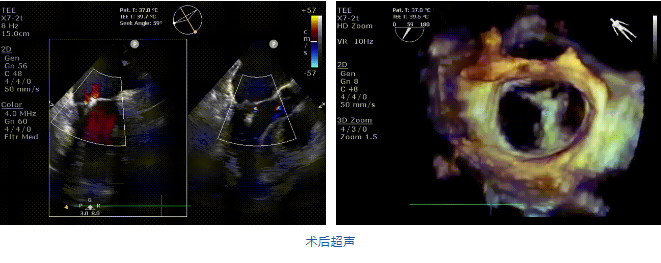

在阜外醫(yī)院潘湘斌教授團隊的支持下,手術經股靜脈-房間隔入路,采用全身麻醉插管,在TEE和DSA引導下完成房間隔穿刺。置入JensClip瓣膜夾系統(tǒng)后,在左房調整瓣膜夾的位置和軸向,后進入左室,在TEE引導下捕捉二尖瓣前后瓣葉,并關閉瓣膜夾。經TEE反復確認手術效果后最終鎖定并釋放瓣膜夾。術后即刻超聲顯示瓣膜夾位置穩(wěn)定,功能良好,二尖瓣反流由術前4+減少至微量,手術圓滿成功。